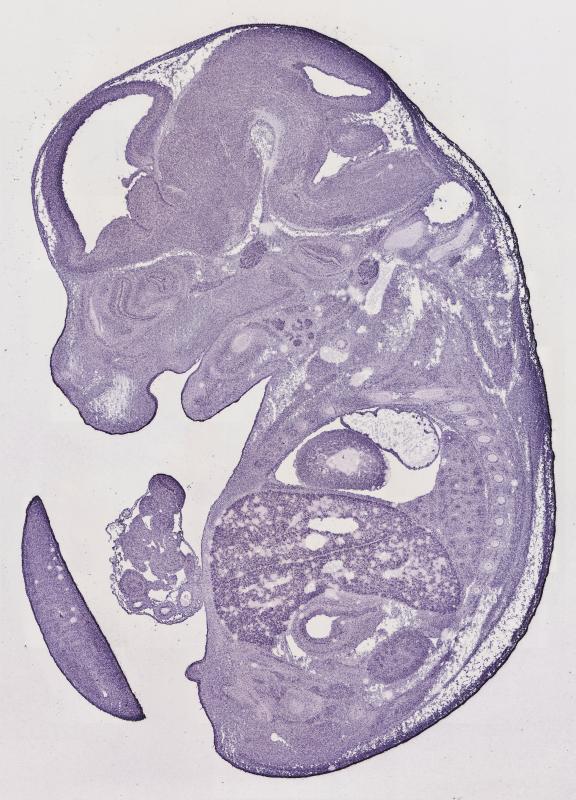

early conceptus |

embryo ectoderm |

embryo endoderm |

embryo mesoderm |

embryo mesenchyme |

extraembryonic component |

alimentary system |

auditory system |

branchial arches |

cardiovascular system |

connective tissue |

endocrine system |

exocrine system |

hemolymphoid system |

integumental system |

limbs |

liver and biliary system |

musculoskeletal system |

nervous system |

olfactory system |

reproductive system |

respiratory system |

urinary system |

visual system |